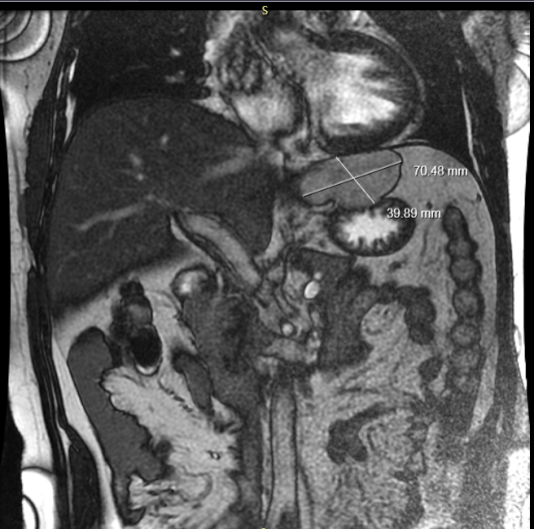

患者男性,49岁,因“发现双侧腹股沟区可复性包块21+年,再发17年”入院。入院阴囊及双侧腹股沟淋巴结B超示:双侧腹股沟疝。腹部B超示:肝左叶后方低回声团块,胆囊腔内异常回声:泥沙样结石或胆泥?上腹部X线计算机体层(CT)平扫(膈顶至脐),上腹部X线计算机体层(CT)增强扫描示:肝左外叶血管瘤考虑(5.9cm*7.1cm)。

图一为肝血管瘤

图二为病变胆囊及肝血管瘤